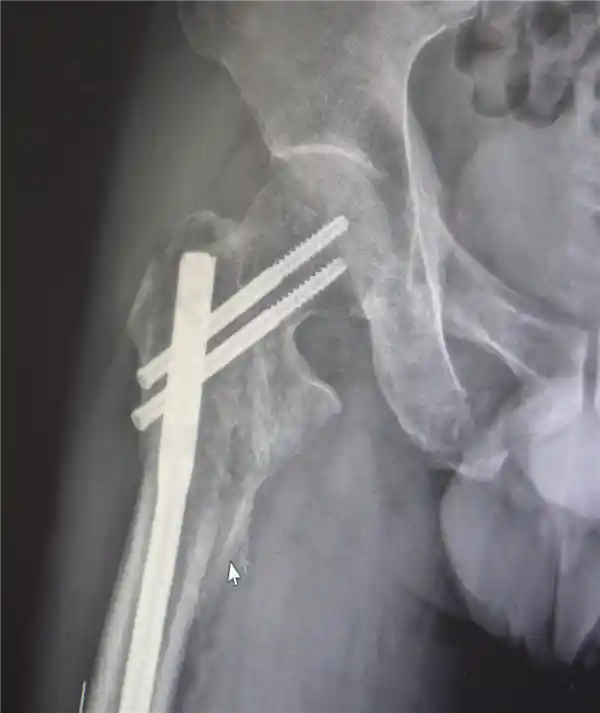

创伤性失血性休克、多发性肋骨骨折、肺部损伤、右侧肩胛骨粉碎骨折、右侧肱骨髁上开放粉碎性骨折、右股骨粗隆及股骨干粉碎性骨折、骨盆粉碎性骨折、腰椎横突多发骨折、腰骶柱神经损伤、臂丛神经损伤、胸腔积液、腹腔积液等。

经医生检查,张先生全身共有六处较大骨折部位,多为严重粉碎性骨折,全身骨折碎块达30多块!

最终医疗团队运用了类似修复古董瓷器的“拼古董”复位固定技术,先将大块骨片进行拼接,再处理小块骨片,先后实施了两次手术。

部分手术后拍摄的影像